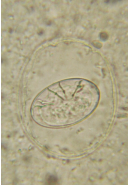

Crenosoma striatum (личинка I)

| Цикл | Взрослый червь живёт в бронхах ежа. Его личинка I откашливается, проглатывается и выводится с калом. Выведенные личинки попадают в червей и развиваются там до инфекционной личинки III. Когда ёж съедает заражённого червя, круг замыкается: через лимфу и кровь личинка III попадает в лёгкие ежа. |

| Инкубационный период | 3 недели |

| Течение | Единичные поражения паразитом или бактериальной вторичной инфекцией могут привести к тяжелой бронхопневнмонии. При отсутствии лечения – часто с летальным исходом. |

| Симптомы | Кашель, чихание, одышка (вплоть до ортопноэ), выделения из носа, отсутствие аппетита, истощение, общее возбужденное состояние. |

| Диагноз | Личинки в кале |

| Терапия | Левамизол (средство на выбор), Моксидектин. Антибиотики при бактериальной вторичной инфекции, муколитика, замена жидкостей. |